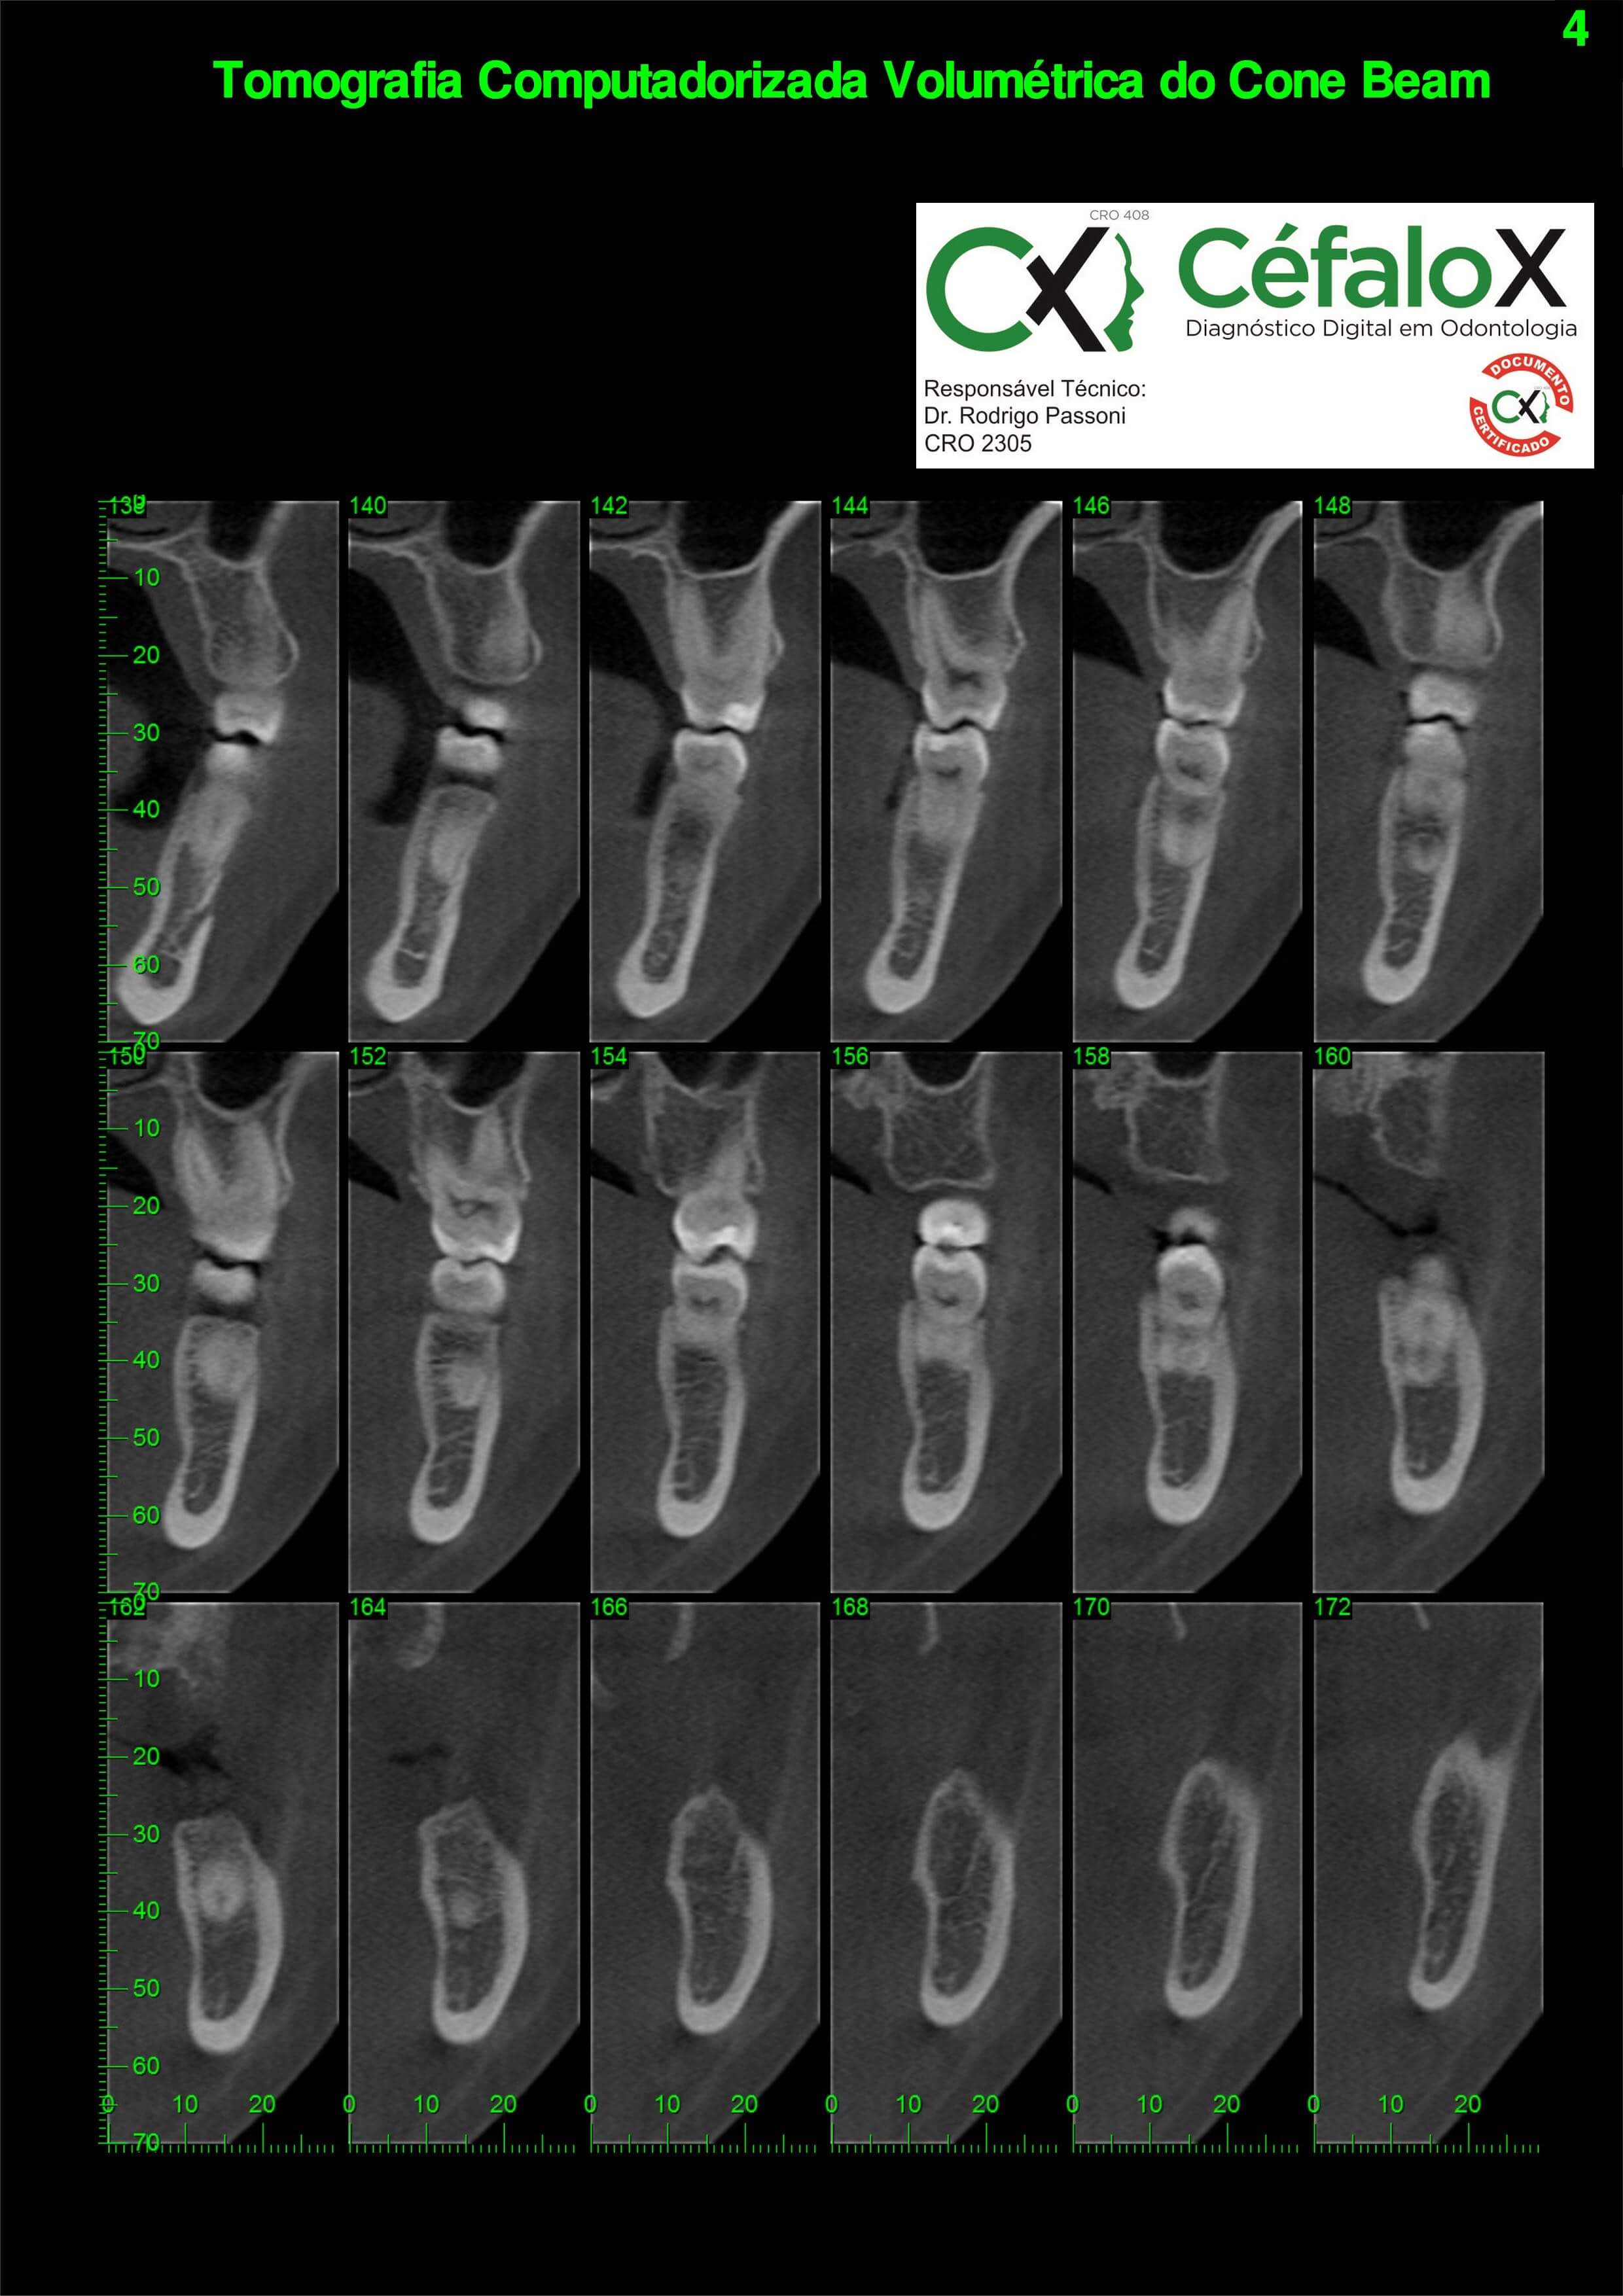

TC de face (do Hióide à Glabela), reconstrução 3D do tecido ósseo, radiografia panorâmica, telerradiografia lateral com traçado, cortes transversais e axial de maxila e mandíbula e arquivo DICOM- entregue em pasta de Pvc.

TC de face (do Hióide à Glabela), reconstrução 3D do tecido ósseo, radiografia panorâmica, telerradiografia lateral e frontal com traçado, cortes transversais e axial de maxila/mandíbula e arquivo DICOM – entregue em pasta de Pvc.

TC de face (do Hióide à Glabela), reconstruções 3D do tecido mole/ósseo/vias aéreas, radiografia panorâmica, telerradiografia lateral e frontal com traçado, cortes transversais e axial de maxila/mandíbula, ATM e arquivo DICOM – entregue em pasta e caixa de Pvc.